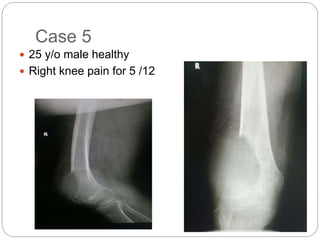

This document discusses 8 oncology cases. Case 1 involves a 40-year old female with right knee pain. Case 2 is a 28-year old male with a left subtrochantric fracture from a MVA who is now experiencing increasing left knee pain and swelling. Biopsy results showed high-grade osteosarcoma. Case 3 is a 30-year old female with breast cancer and bone metastases causing bilateral hip pain.